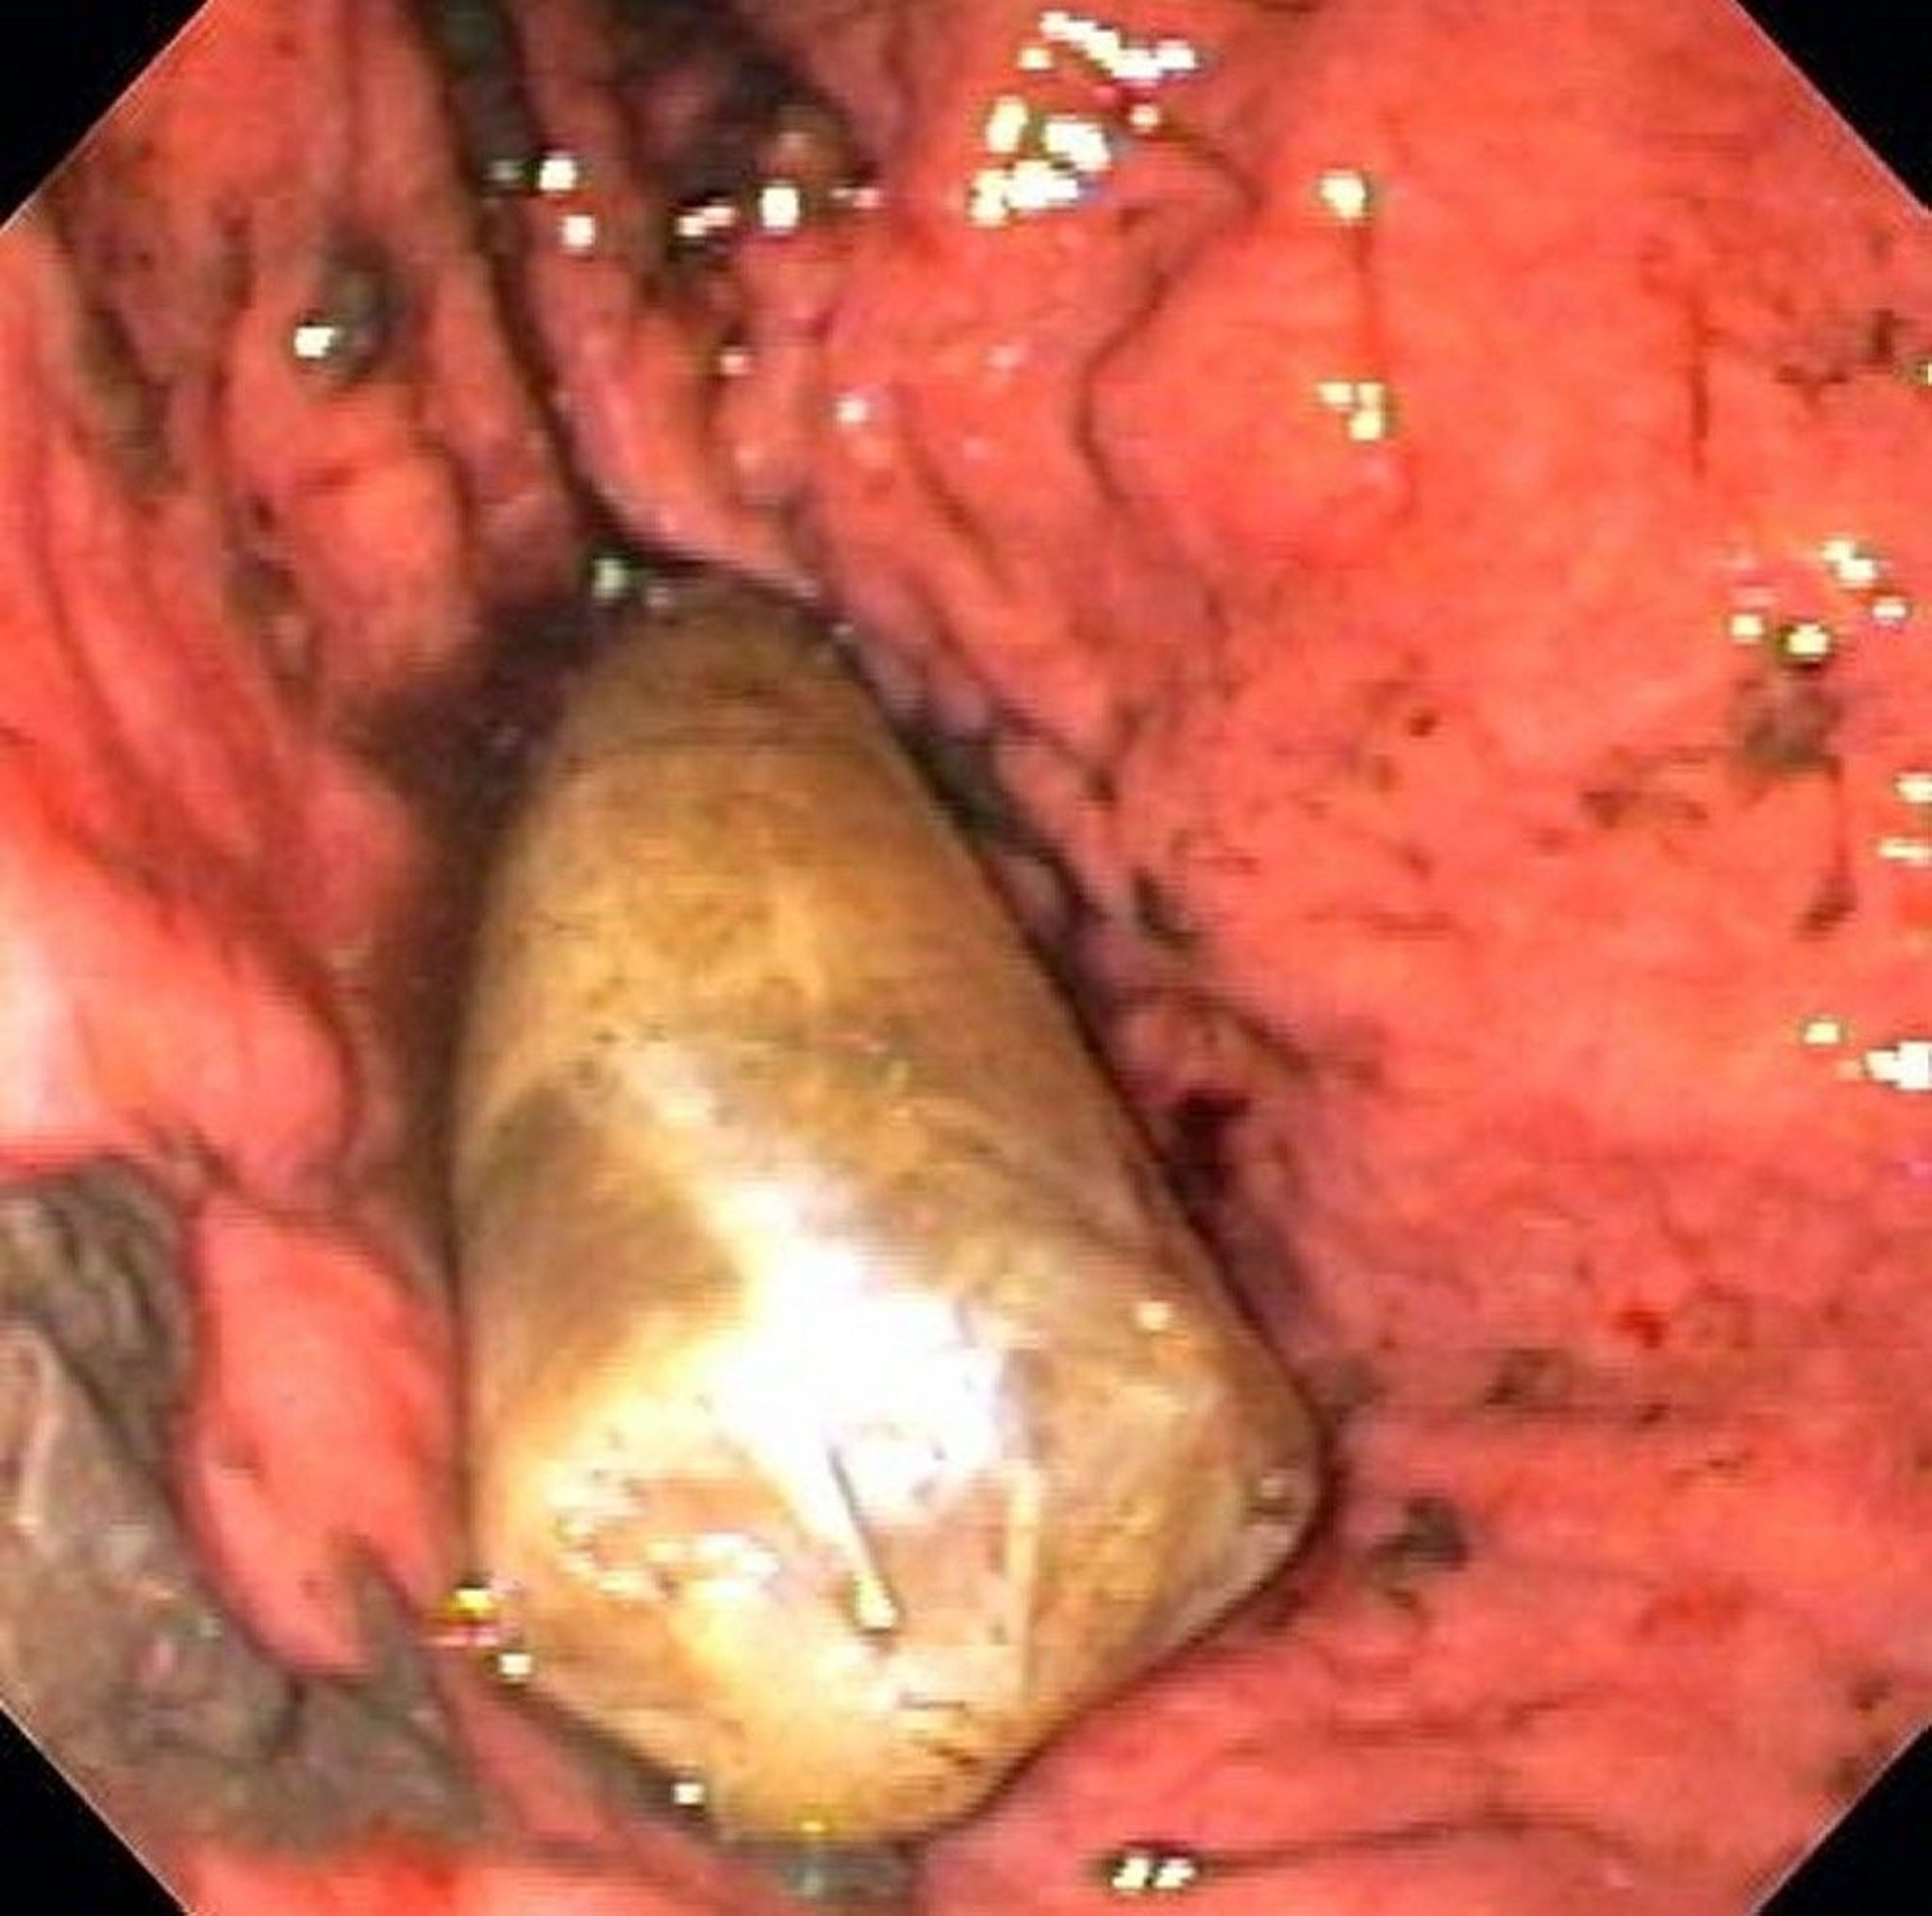

Foreign Body in the Stomach (Endoscopy)

This image shows a drug packet in the stomach.

Image provided by Alan Gingold, DO.